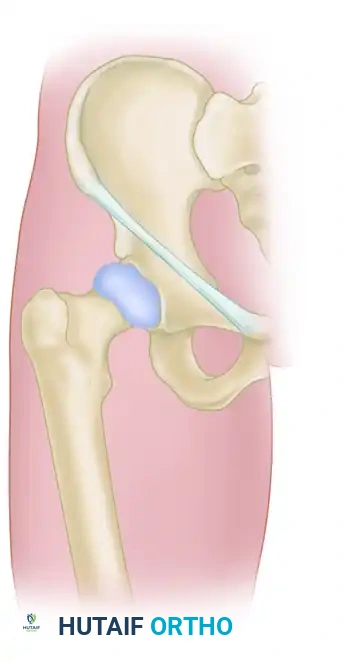

ADJUNCTIVE TECHNIQUES: ANTERIOR APPROACH AND STABILIZATION

While percutaneous posterior fixation is the workhorse of pelvic trauma, certain injury patterns—such as highly unstable crescent fractures or chronic SI joint disruptions—may require direct open reduction and internal fixation via an anterior approach.

Anterior Plating of the Sacroiliac Joint

When an anterior approach is indicated, the patient remains supine. An incision is made along the anterior iliac crest, extending distally toward the anterior superior iliac spine (ASIS). The iliacus muscle is elevated to expose the anterior aspect of the sacroiliac joint.

After direct visualization and reduction of the joint, stabilization is achieved by fixing the sacral ala to the ilium. This is typically performed using two orthogonal, two-hole or three-hole dynamic compression plates (or specialized pelvic reconstruction plates) placed across the anterior SI joint.

Image

This anterior plating technique provides excellent biomechanical stability against external rotation forces and can be used in conjunction with posterior percutaneous screws for maximal construct rigidity.